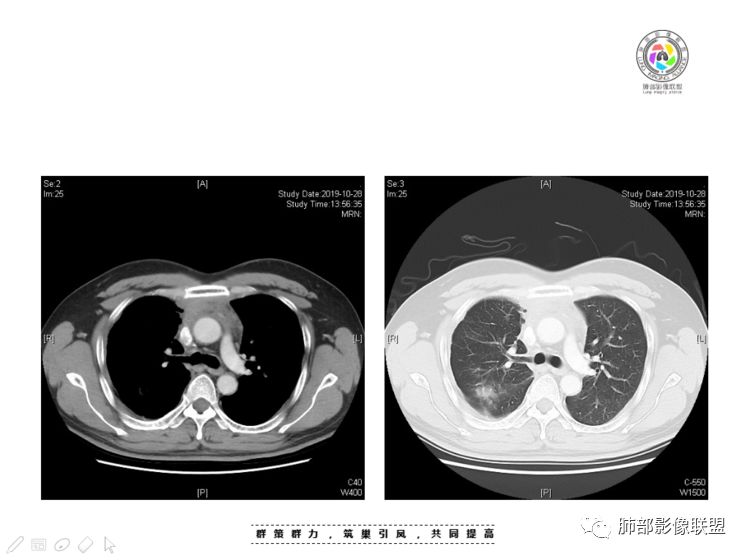

肺内结节,近端支气管堵塞狭窄

整体边缘收缩,部分膨隆

炎性要考虑,但恶性不能排除

1、右肺内病灶,病灶呈结节样,边缘欠规则,局部膨隆,叶间裂胸膜牵拉凹陷,再看相应支气管腔堵塞截断,临床资料胸水中查到癌细胞,均提示病灶倾向恶性,腺癌的病理意见与之相吻合。

黄勇老师总结,腺癌如果与胸膜、叶间裂紧贴或伴胸膜凹陷,胸膜、叶间裂多发结节,应当高度怀疑腺癌转移。

2、前纵隔内病灶囊实性混杂密度病灶,囊性病灶主要位于右侧,张力较高,有分隔影,囊壁右侧缘光整,病灶左侧实性部分边界不清明显强化,病灶肺瘤交界面大部分边界清楚,部分模糊。

胸腺瘤/胸腺癌:病灶内那么大的囊,常规考虑B型以上胸腺瘤,囊内有分隔影,病灶周围脂肪间隙模糊,常规考虑侵袭性胸腺瘤或胸腺癌,若侵袭性胸腺瘤,常侵犯胸膜、心包,很少累及肺。胸腺癌易侵犯胸膜、肺并纵隔淋巴结及远处转移。但肺内腺癌形态更符合原发灶。胸膜及叶间裂转移则即可来自肺,也可来自胸腺癌。

尽管前纵隔病灶缺乏相关病理资料,但是小编还是认为肺内与纵隔病灶以二元论解释。只是肺内恶性病灶引发的胸膜改变可能会影响我们对纵隔病灶的判断。